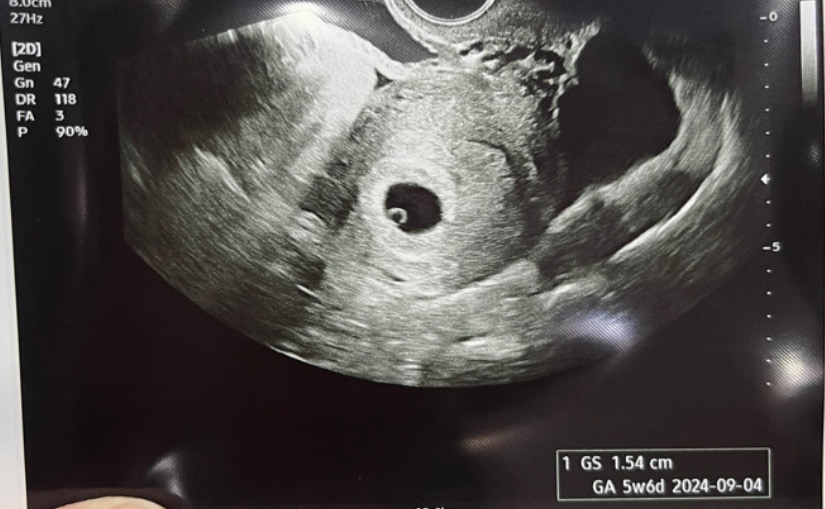

아기집 보고 왔어요💗

다음주에 심장소리들으러 오라고 하셨어요💗 잘 크고 있다고 하셔서 넘 신기해요👶🏻 혹시 초음파 못볼까봐 기다리고 기다리다 갔는데 넘 신나네요🥰